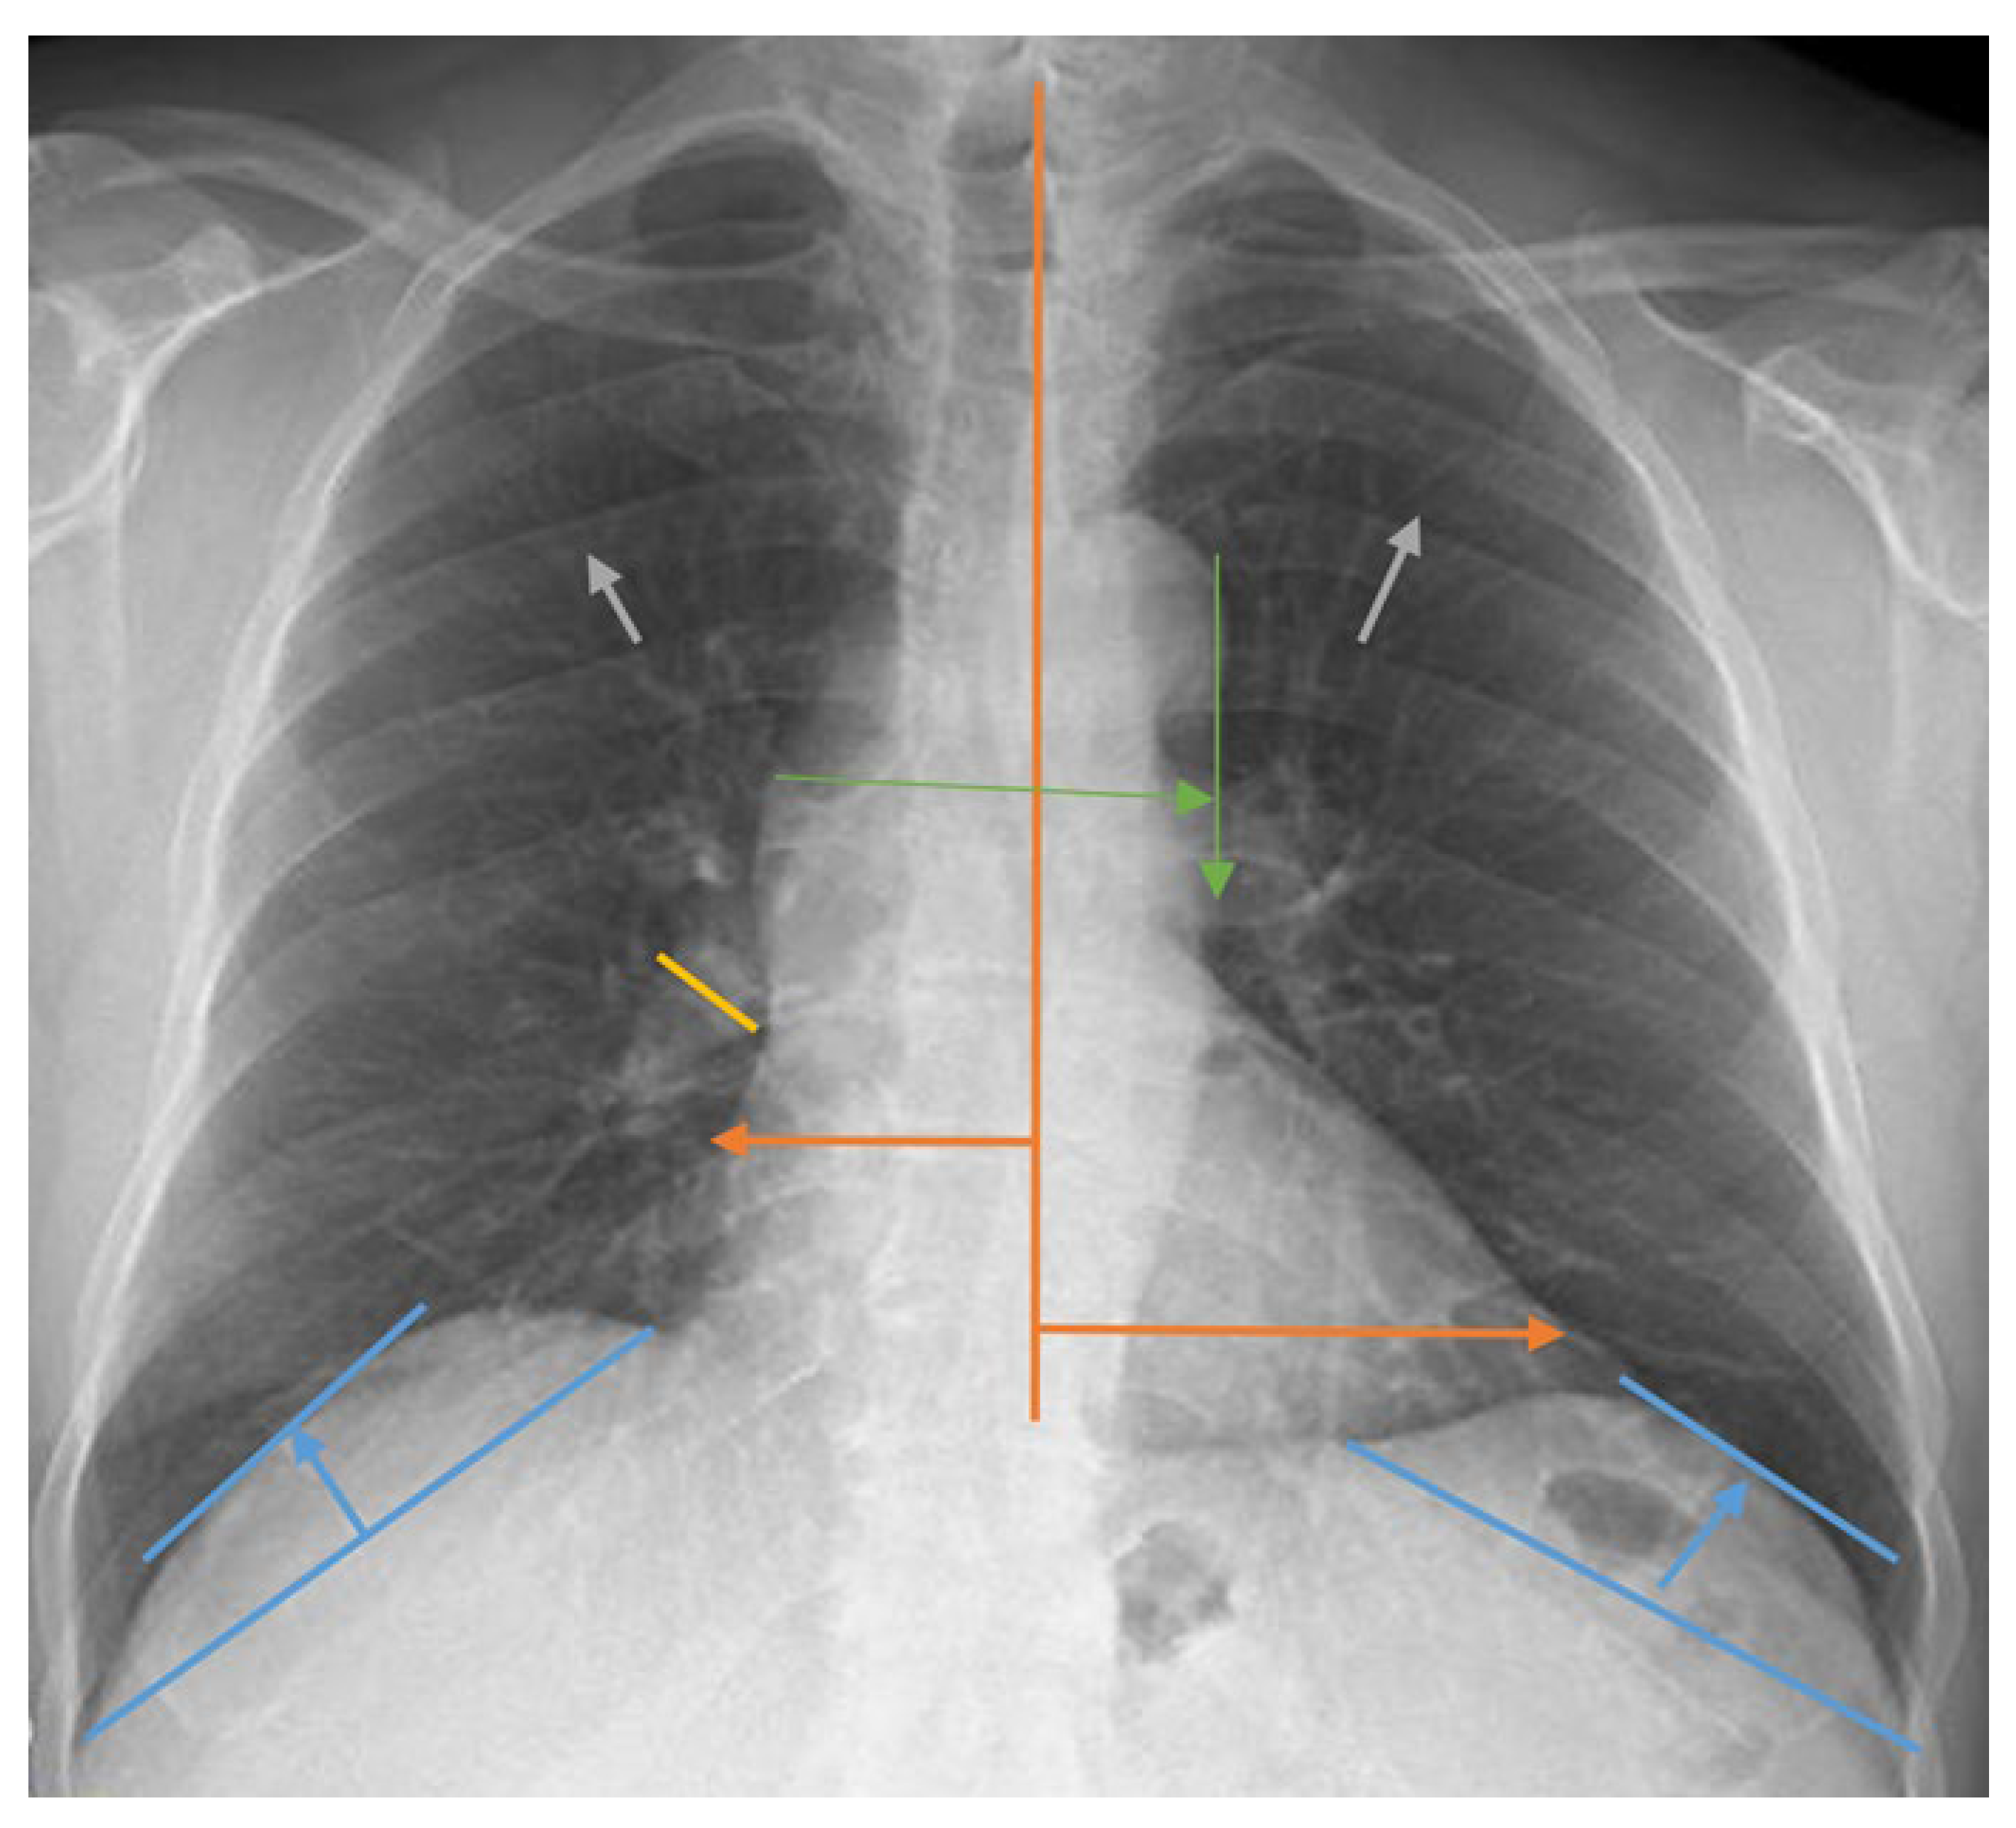

2.2. Lung Radiograph Measurement Calculations

- Wang, H.; Shi, R.; Mahler, S.; Gaspard, J.; Gorchynski, J.; D’Etienne, J.; Arnold, T. Vascular pedicle width on chest radiograph as a measure of volume overload: meta-analysis. West. J. Emerg. Med. 2011, 12, 426-432. [CrossRef]

- Elasan, S.; Yilmaz, O. Cardiothoracic ratio and left ventricular ejection fraction relationship: A meta-analysis study. Saudi Med. J. 2023, 44, 529. [CrossRef]